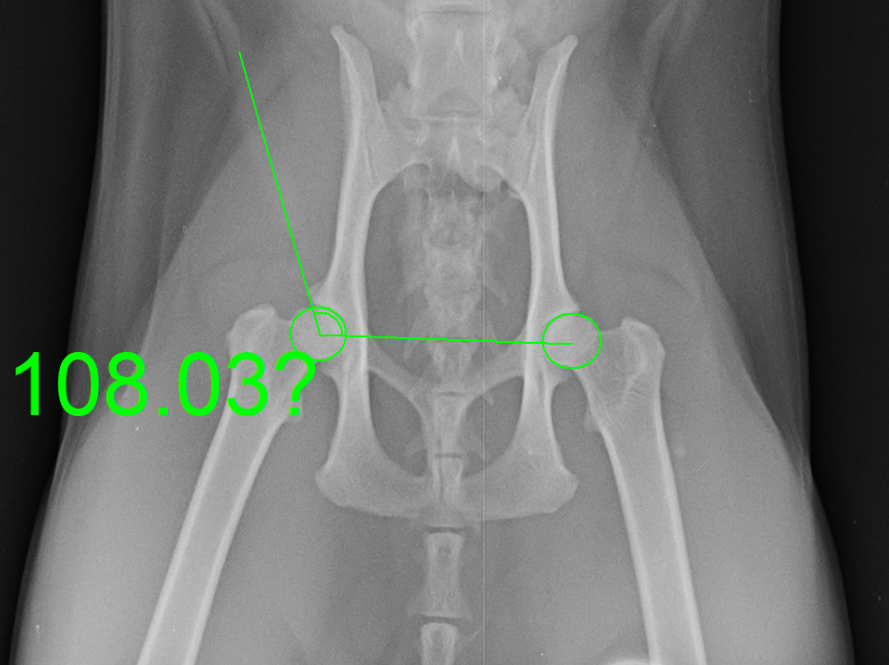

Norberg angle in dog and cat : ref. value

in dogs : 105 degrees

in cats : 95 degrees